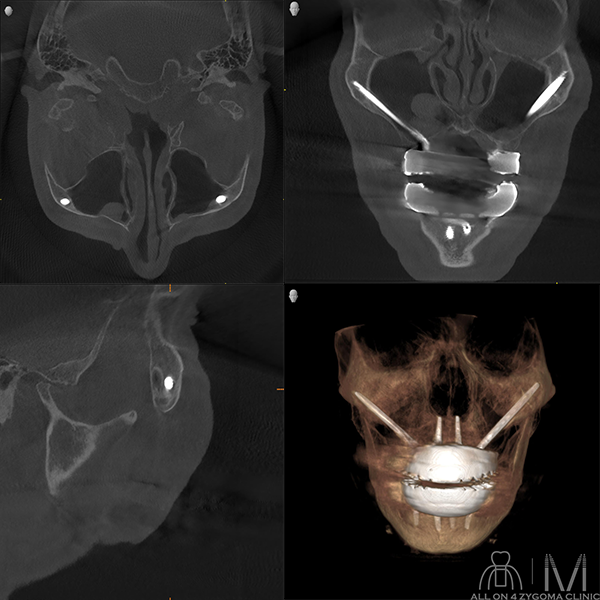

最終補綴物セット後のCT画像所見